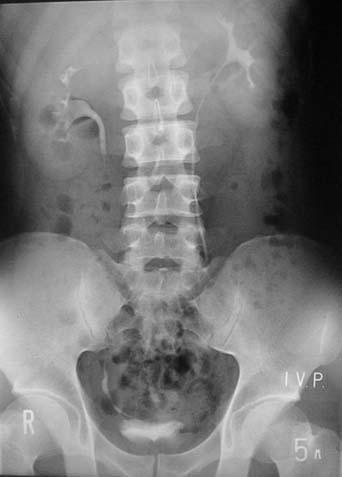

5分後の写真

造影剤注射後5分の写真

主に腎機能を見ます。

腎臓で濾過されたおしっこ(造影剤)が写ってきています。

わかりますか?